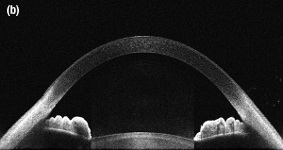

An Image of the Anterior of the Eye Taken with the SLD830S-A10 in a Modified Ganymede ll OCT System

OCT Application Images

SLD830S-A10 (sold below) as a light source. The images each have an in-tissue depth of 6.2 mm and were taken using a 36 kHz A-scan rate.